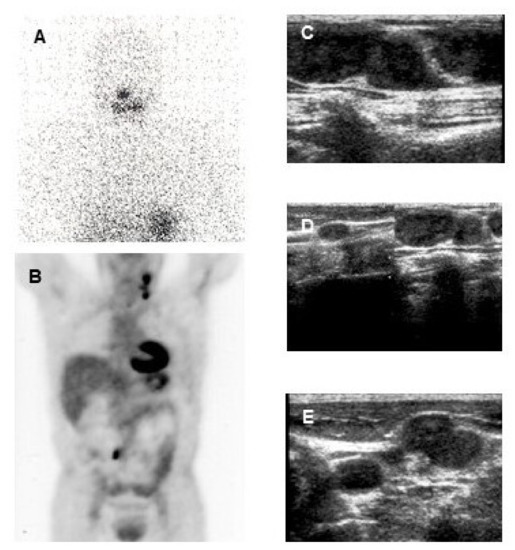

Indeed, PET/MR when available might be performed in selected patients with bone, soft tissue or liver lesions for whom a MR imaging is indicated (Figure 4).

Figure 4.

Classical papillary thyroid cancer in a 45-year-old man18F-FDG PET-CT (A,B) and 18F-FDG PET-MR (C,D) show a mediastinal lymph node with high 18F-FDG uptake.